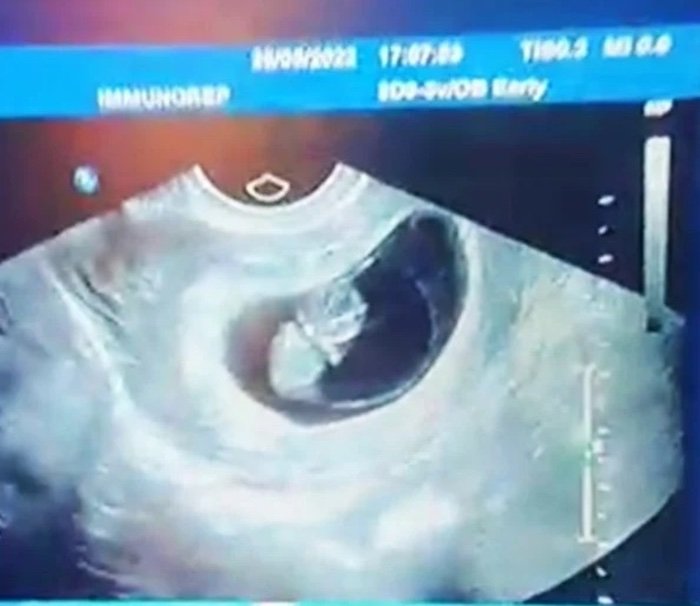

De igual forma compartió detalles de su embarazo y las primeras imágenes de su bebé: “Pues tengo 13 semanas, todo está bien. Ha sido algo superbonito, que todavía no me lo creo, pero que aquí está y efectivamente estoy embarazada”, sentenció.